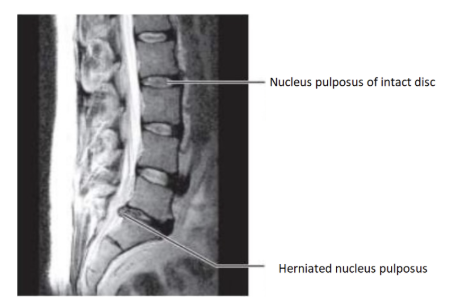

<p>The MRI of the vertebral column of the lumbar region above is in a ____ section showing a herniated disc</p>

The MRI of the vertebral column of the lumbar region above is in a ____ section showing a herniated disc

saggital